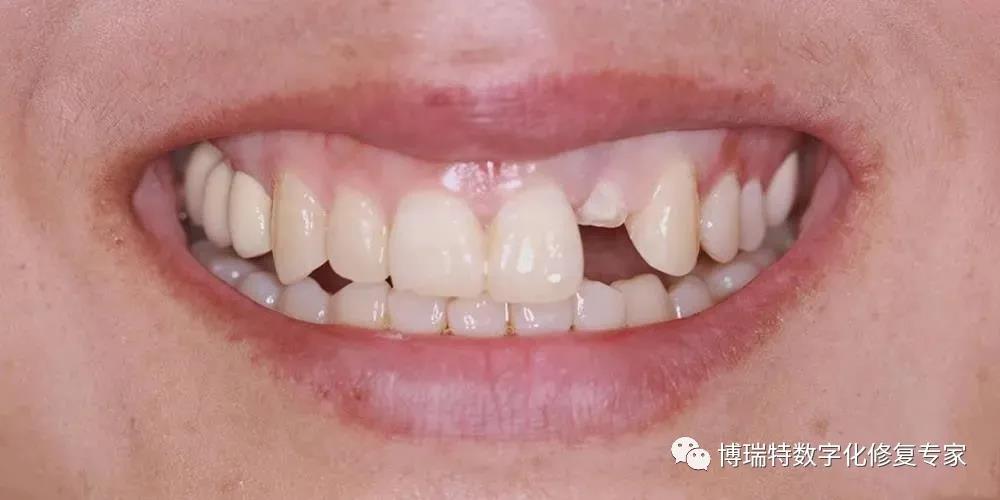

8226; 高位笑线,牙龈色粉,质韧,无明显红肿;

8226; 薄龈生物型,角化龈宽度充足,龈缘高度不协调;

8226; 21龈缘根向移位约1mm;

8226; 张口型张口度正常;